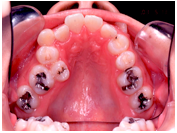

• 歯を抜くかどうかは、矯正治療をする上で非常に重要な問題です。そこで、治療方針を決める際にはまず検査をし、その検査結果を分析します。もちろん患者さんの希望も考慮にいれて、診断の際に最終的な判断をします。

• 歯を抜く場合には、どうして抜かないといけないのか、何本抜くのか、またどの歯を、いつ、どこの歯科医院で抜くのか(当クリニックでは、抜歯はゆきつけの歯科医院へお願いしています)などを分析資料を交えて説明致します。抜歯したスペースは、矯正治療によりどのように利用されますので、隙間が残ることはまずありません。抜く場合にはそれによりかみ合わせや、横顔等がどう変化するのかも、予測画像をお見せすることもできます。